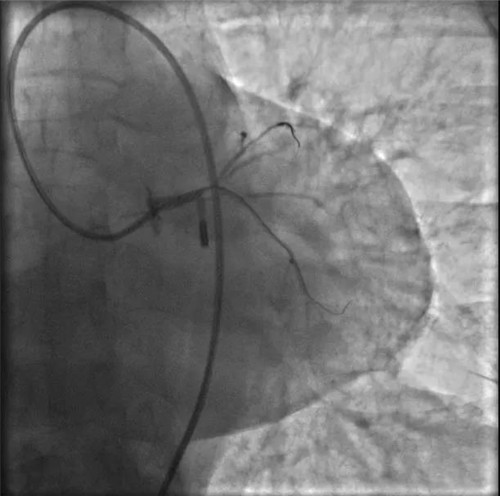

IABP(主動脈內(nèi)球囊反搏)

突發(fā)的狀況并沒有打亂團(tuán)隊的陣腳,待生命體征穩(wěn)定后,決定先植入IABP(主動脈內(nèi)球囊反搏)提供循環(huán)支持,防止病情進(jìn)一步惡化。穿刺雙側(cè)股動脈,分別置入IABP導(dǎo)管及左冠指引導(dǎo)管。

因患者股動脈扭曲,導(dǎo)管操控困難,術(shù)者反復(fù)嘗試,以導(dǎo)絲飄進(jìn)左主干,在球囊的支撐下,通過閉塞段到達(dá)中間支,小壓力擴張后造影可見主干末端嚴(yán)重狹窄。隨后小心操控導(dǎo)絲到達(dá)回旋支、前降支,送入球囊擴張,嚴(yán)重狹窄的左主干末端被撐開,左冠血流終于恢復(fù),胡女士暫時轉(zhuǎn)危為安。

球囊擴張后,左冠血流恢復(fù),但左主干末端重度狹窄